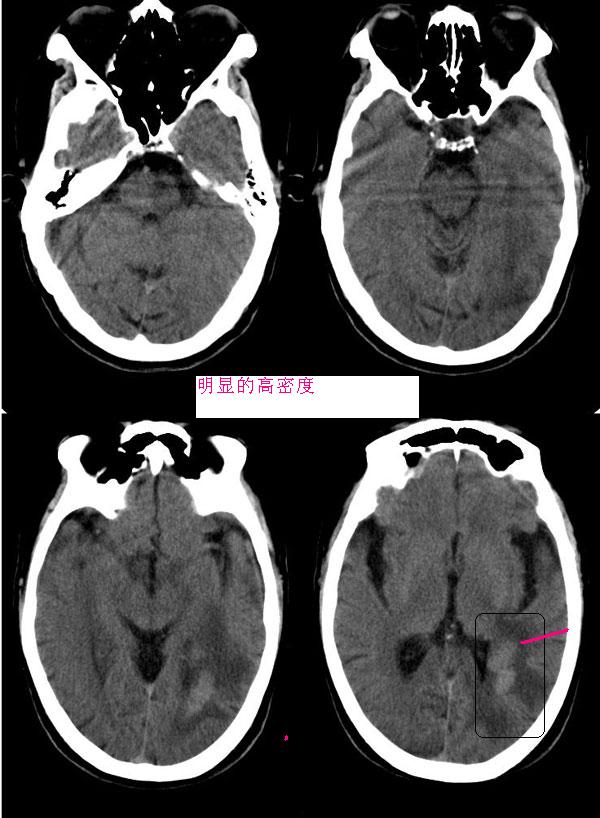

病灶平扫ct值约38hu,强化后明显强化,ct值约63hu,有一层ct值约72hu,病史:病人,男75,血压120/75,不高,头晕12天,平时体健,当时曾作胸x线片,正常。腹部ct,肝多发囊肿。经治疗(林格液+甘露醇)未用营养液及化疗药,当时诊断转移瘤。12天复查片如下

胼胝体见多个明显强化结节影,周围水肿轻,左颞枕交界区见呈腊肠状强化灶,周围水肿明显,多发病灶均有占位效应,首先考虑淋巴瘤,水肿轻,位置深,强化明显,其次转移瘤?

胼胝体见多个明显强化结节影,周围见低密度水肿灶;左颞枕交界区见呈腊肠状强化灶,增强后强化明显,周围指状水肿。多发病灶均有占位效应,水肿轻,位置深,强化明显。

胼胝体膝部及压部各见一明显强化结节影,周围水肿轻,左颞枕交界区见呈腊肠状强化灶,周围水肿明显,多发病灶均有占位效应。

左颞枕交界区及胼胝体多发明显而均匀强化的实性肿块。

沟脑回加深增宽证像,特别是双侧外侧裂池增宽明显,因是老年患者,病灶位置深且都在侧脑室旁,呈腊肠状,边界清,有轻占位和水肿。

首先考虑淋巴瘤;转移瘤也可考虑,但病灶虽为多发,但位置深在,与其好发于大脑皮质及皮质下区的特点不符。